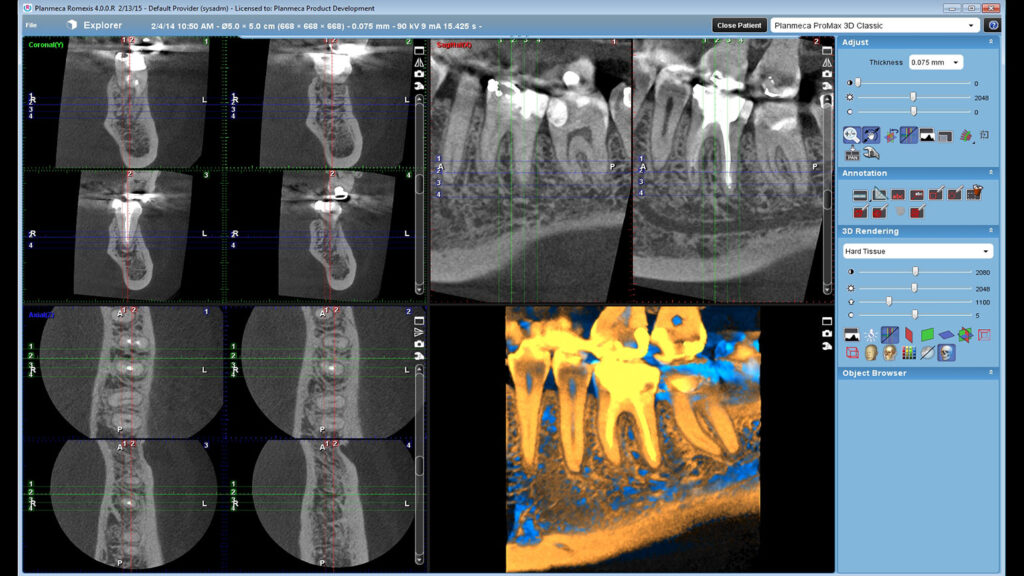

Endodontic imaging mode

• Veoma visoka rezolucija, veličina voxela 75 µm – perfektna slika za fine anatomske detalje

Primena CBCT snimka u oblasti endodoncije:

• Procena komplikacija endodontskog lečenja

• Dg periapikalne patologije

• Komplikovan sistem kanala korena

• Utvrđivanje zakrivljenosti kanala korena

• Dg traume – fraktura korena, alveolarnog nastavka, luksacije

• Lokalizacija resorpcije korena

• Određivanje tačne lokalizacije apexa korena u prehirurškom planiranju

• Tačne mere

Malo polje Ø40×50 mm – Visoka rezolucija, veličina voxela 150 µm

Srednje polje Ø68×68 mm, niska rezolucija velicina voksela 600 µm